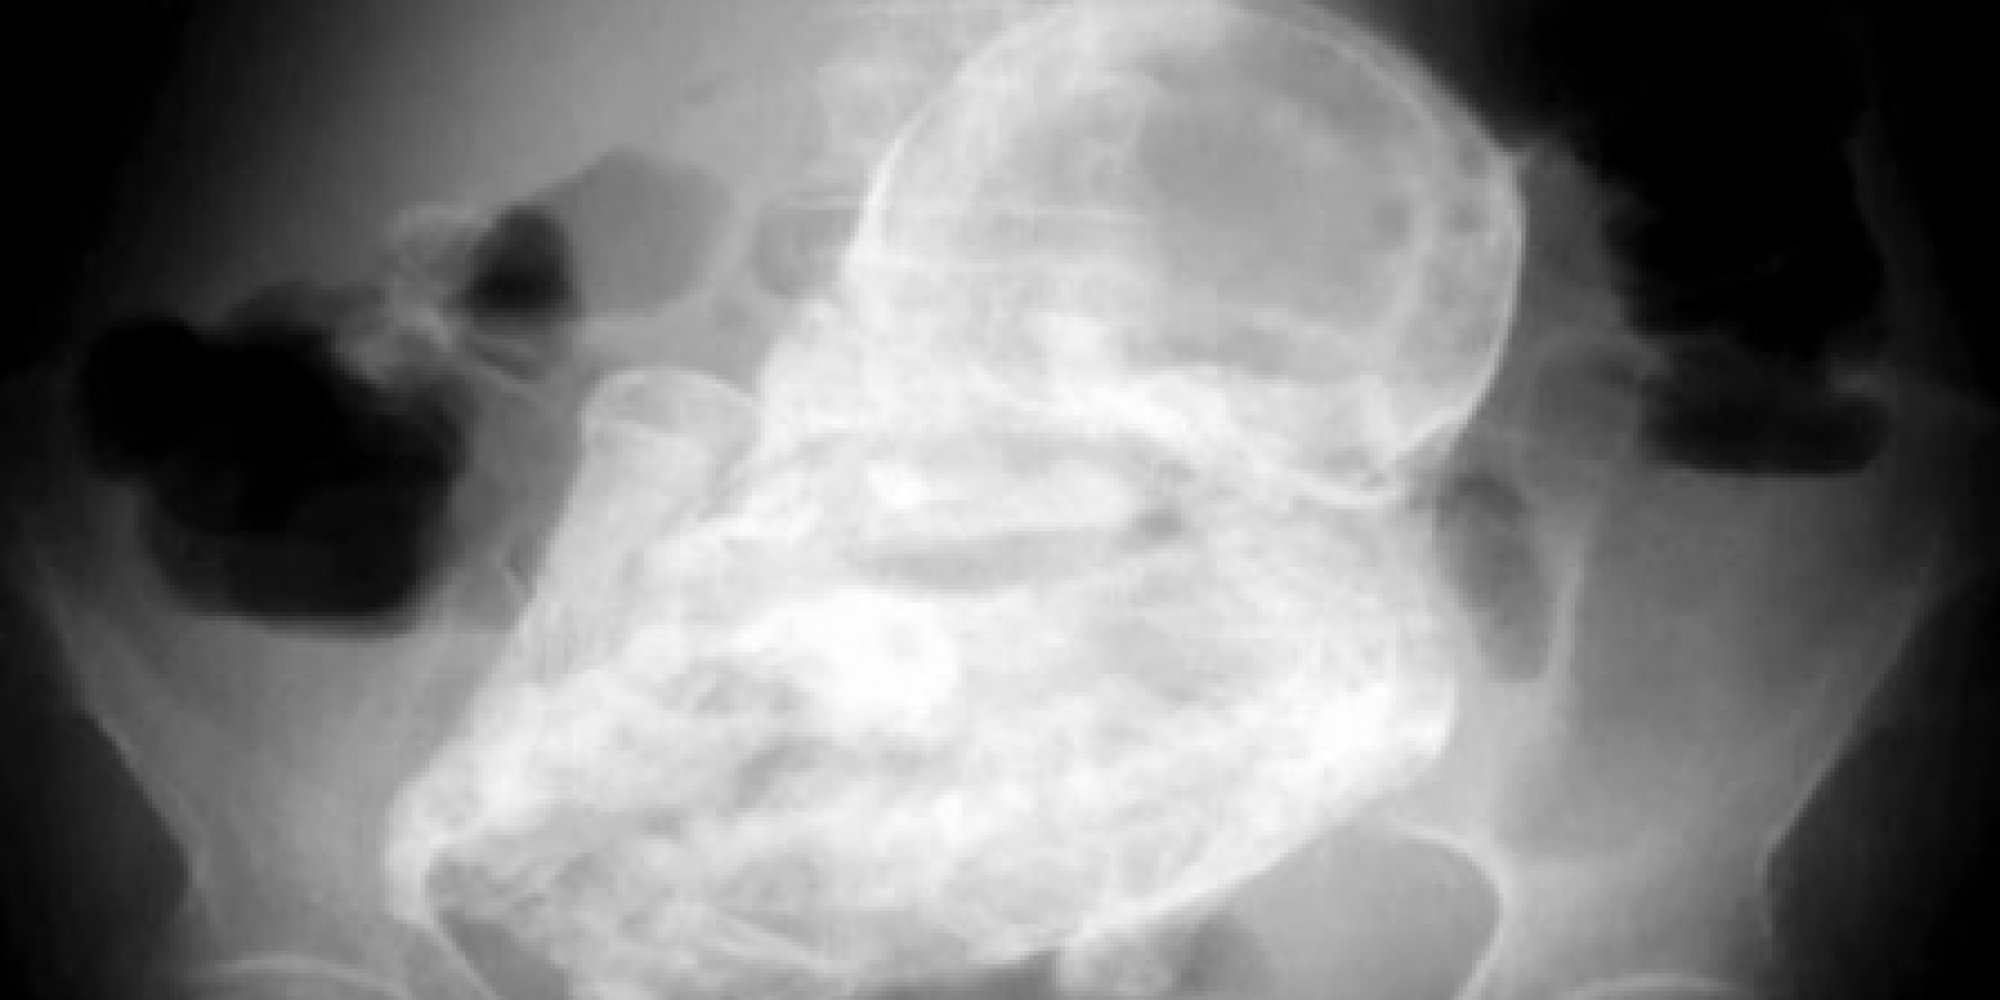

An 82 year old woman from Bogota, Colombia who was suffering from stomach pain was found to have a 40-year-old fetus inside her. She had what is called ‘lithopedion’, or stone baby, a condition where the unborn baby develops outside the womb.

Before she went to the hospital, the woman was thought to be suffering from a stomach bug but scans revealed lithopedion, where the foetus becomes calcified. There are fewer than 300 cases reported in medical literature.

An ultrasound showed nothing then radiography of her abdomen revealed a tumour in her abdominal cavity.